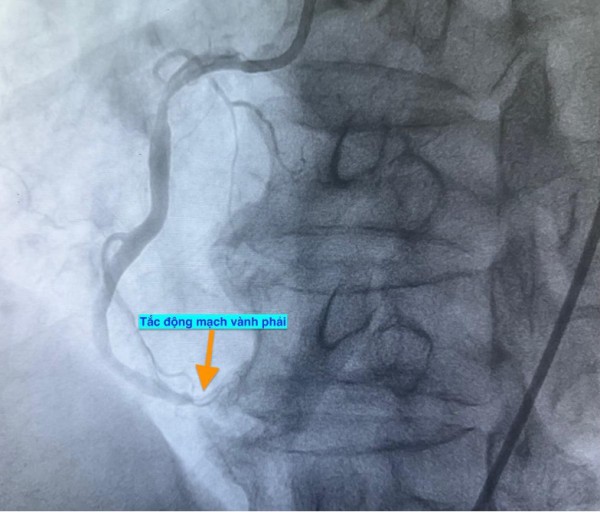

Trường hợp thứ hai, lúc 9 giờ 5 phút, nam bệnh nhân 53 tuổi nhập viện vì chóng mặt và nóng rát thượng vị. Điện tâm đồ ghi nhận nhồi máu cơ tim cấp vùng dưới. Kết quả chụp mạch vành xác định bệnh nhân cũng bị tắc động mạch vành phải.

Hình ảnh chụp mạch vành cho thấy các bệnh nhân bị tắc mạch máu tim (do mảng xơ vữa, huyết khối) dẫn đến tình trạng thiếu máu cục bộ và nhồi máu cơ tim cấp

ẢNH: BV